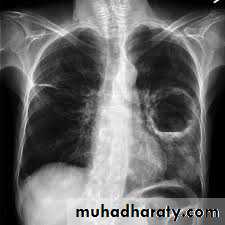

1. CXR 2. CT scan

1) well defined circular or oval homogenous opacity

2) perivesicular pneumocyst or signet ring sign

4) Bilateral and multiple cysts